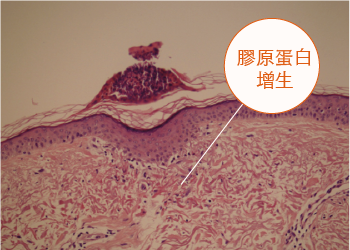

而接受療程後第五天,真皮層內的膠原蛋白數量明顯增加, 表皮傷口亦已經癒合。

療程後第五天

病人PG - 療程後5日:良好的癒合,並形成細小的結痂範圍(最大直徑可達0.25毫米) 結痂下面有被改變了的膠原蛋白 (高達0.20毫米)

病人PG

良好的癒合,

並形成細小的結痂範圍

(最大直徑可達0.25毫米)

結痂下面有被改變了的膠原蛋白

(高達0.20毫米)